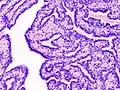

Intraductal papillomas of the breast are benign lesions with an incidence of approximately 2-3% in humans.[1] They result from abnormal proliferation of the epithelial cells lining the breast ducts.[2]

Two types of intraductal papillomas are generally distinguished. The central type develops near the nipple. They are usually solitary and often arise in the years nearing menopause. On the other hand, the peripheral type are often multiple papillomas arising at the peripheral ducts, and are usually found in younger women. The peripheral type are associated with a higher risk of malignancy.[3]